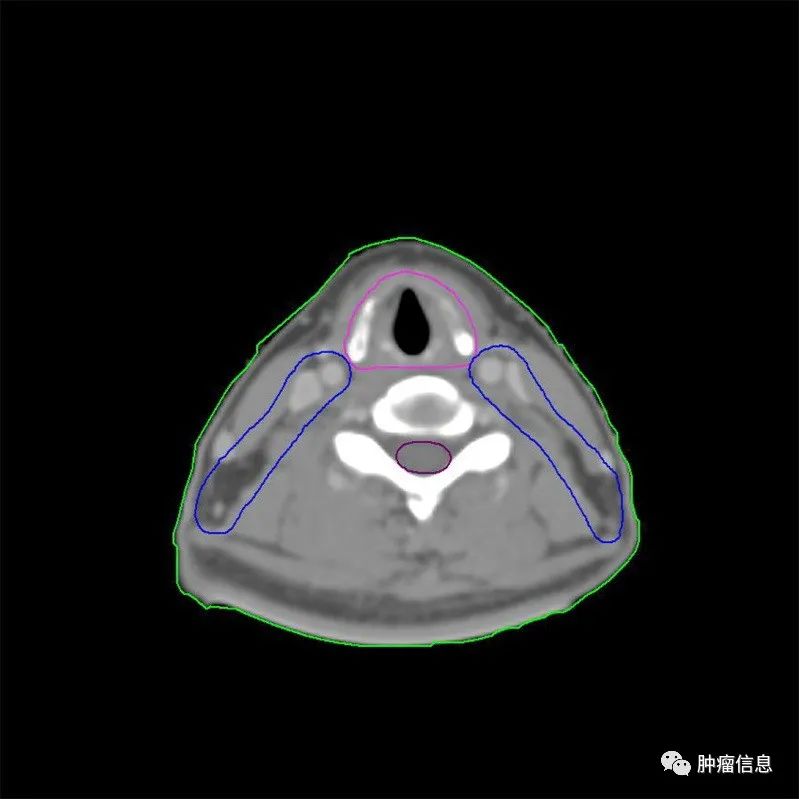

2.靶区勾画示意图

为方便和国际指南对照,靶区采用与国际指南相同的颜色:国际指南的GTVp =本示意图GTVnx;国际指南的GTVn =本示意图GTVnd;国际指南的CTV1 =本示意图CTV1;国际指南的CTV2 =本示意图CTV2。

图1 T1N0M0

(注:靶区勾画颜色, GTVnx为红色,CTV1为绿色,CTV2为蓝色。)